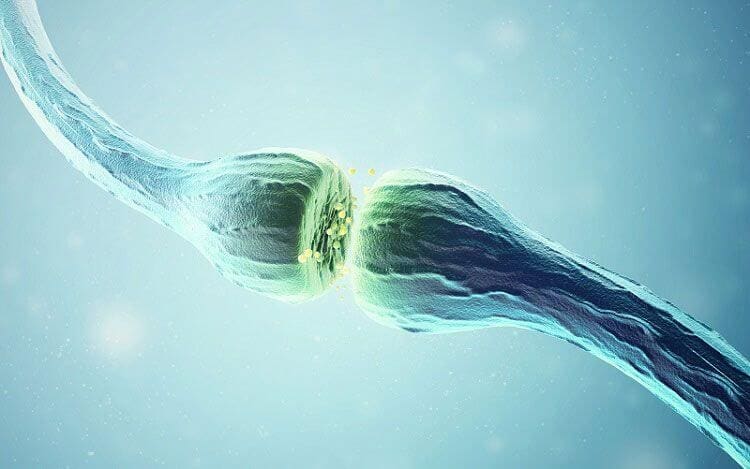

نغطي كل التخصصات الطبية

استیعاب کافة الحالات الطبیة لشمولیة التخصصات

مقالات طبية من مساهمات الأطباء